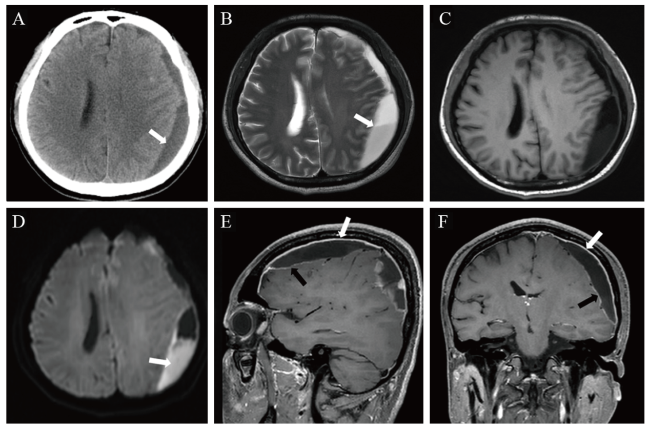

术后患者头痛缓解,术后12 d(2020年10月17日)脑脊液检查提示,蛋白246.6 mg/L(参考值范围80~430 mg/L),葡萄糖2.33 mmol/L(参考值范围2.2~3.9 mmol/L),氯化物132.4 mmol/L(参考值范围118~132 mmol/L),白细胞22×106/L(参考值范围0~8×106/L),球蛋白阳性。2020年10月20日复查颅脑MRI,提示左侧额顶部骨质内板下异常信号影范围明显缩小,额顶部硬脑膜及额顶叶软脑膜增厚,左侧顶叶片状低T1WI、高T2WI信号,提示脑实质水肿(图2A)。患者病情好转后出院。2021年2月5日,患者返院随访,未述不适,入院体格检查:患者神志清晰,反应正常,口腔未见白色伪膜,颈软无抵抗,生理反射存在,病理反射未引出。入院后实验室检查:超敏CRP 1.89 mg/L,血清淀粉样蛋白A 4.1 mg/L,IL-6 2.73 pg/L,ESR 16 mm/h,CD4+ T淋巴细胞计数242.75 /μL(参考值范围410~1 590 /μL),HIV RNA 检测阴性。复查颅脑CT示,左侧额顶部硬膜下低密度影完全消失,脑实质内未见异常密度(图2B)。

图2 一例艾滋病合并伤寒沙门菌感染致硬膜下脓肿患者随访影像学检查结果

注:A为颅脑MRI平扫T2FLAIR,检查时间为2020年10月20日,示左侧额顶部骨质内板下少许低信号影(黑箭头),左侧额顶部硬脑膜增厚(白箭头),左侧额顶叶软脑膜增厚;B为颅脑CT平扫,检查时间为2021年2月5日,左侧额顶部骨质内板下未见异常密度,脑实质内未见异常密度。